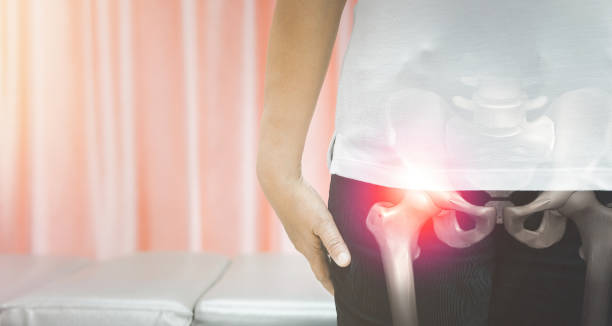

고관절 수술후 회복기간- 수술 후 7주~12주: 운동 및 일상활동의 복귀

7주~12주가 지나면, 조금씩 운동하고 일상활동을 하기 시작할 수 있습니다. 이 때에는 자신의 체력과 회복 상태에 맞게 운동을 시작하고, 일반적인 일상생활에 복귀하면서 천천히 몸의 기능을 복구해 나갑니다. 이 과정에서도 근력 강화와 균형 향상을 위한 운동을 꾸준히 실시해야 합니다.

중요한 점은 회복 기간은 개인의 상태와 수술의 종류에 따라 다르다는 것입니다. 따라서, 의사의 지시에 따라 정확한 회복 기간과 운동 계획을 수행해야 합니다.

또한, 회복 기간 동안에는 휴식과 올바른 영양 섭취도 중요한 요소입니다. 수술 후의 회복 기간을 잘 관리하여 빠르고 안정적인 회복을 이끌어내기 위해 노력해야 합니다.